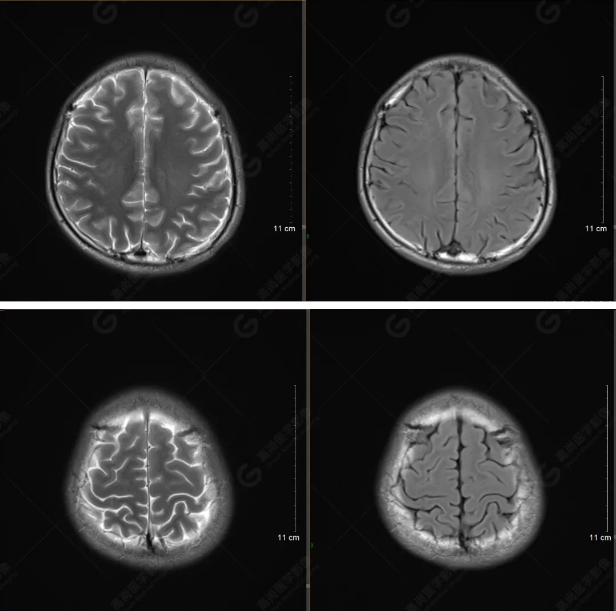

以下是平掃T2WI及FLAIR序列:

雙側(cè)大腦半球?qū)ΨQ,灰白質(zhì)對比正常,顱內(nèi)未見異常信號影。腦室系統(tǒng)未見擴(kuò)大,中線結(jié)構(gòu)居中。腦溝、裂未見增寬。幕下小腦、腦干未見異常。矢狀位示垂體形態(tài)、大小級信號未見異常。所示左側(cè)乳突內(nèi)見多發(fā)短T1長T2信號影。

顱腦MRI平掃未見明顯異常,左側(cè)乳突內(nèi)積血,建議補充SWI檢查。